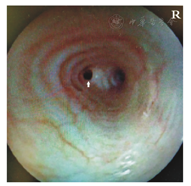

入院辅助检查:动脉血气分析:pH 7.39,PCO2 33.8 mmHg(1 mmHg=0.133 kPa),PO2 44.3 mmHg。血常规:WBC 10.19×109/L,N 37.5%,L 45.4%,RBC 4.8×1012/L,Hb 67 g/L,红细胞压积27.6%,平均红细胞体积57.5 fl,平均红细胞血红蛋白含量14 pg,平均红细胞血红蛋白浓度243 g/L。胸部CT:隆突和双侧支气管结构不清(图1),双侧肺纹理增粗,双肺渗出性病变伴左肺下叶背段高密度影。心脏彩超:房间隔缺损(3.7 mm)。心电图:窦性心动过速。尿常规、便常规、血涂片、肝肾功、心肌酶、血脂、血糖、电解质、传染病、痰细菌培养未见异常。

行支气管镜检查示:气管通畅,隆突结构畸形,隆突水平气管分为左右两支,左侧分支开口狭窄为著(图2)。行CT气管-支气管三维重建示:桥支气管(图3)。建议行手术治疗,患儿家属因手术风险等原因不同意,继续内科保守治疗8 d,病情无缓解,无创呼吸机无法脱机,患儿家属放弃治疗,出院第2天夜间患儿死亡。

隆突结构畸形,气管在隆突水平分为左右两支,左侧开口狭窄,图中箭头所示为显著狭窄的桥支气管开口。